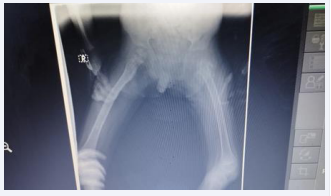

Male patient, 3 years old at admission, white, from rural origin. With a history of good health, until mid-January 2023, which begins with pain in the lower limbs, scrotal edema and difficulty urinating. For this reason, he goes to the pediatric hospital in his native province, where he is admitted and urgently studied, detecting leukocytosis in the blood count and starting treatment with intravenous Ceftriaxone, interpreting the condition as urinary sepsis. When performing a simple anteroposterior and lateral abdominal x-ray, they detected a bladder balloon and opacity at the base of the right hemithorax. An anteroposterior chest x-ray was performed, confirming a radiopaque lesion that occupied the middle and lower third of the right lung.

It was agreed in this discussion to perform Fine Needle Aspiration Biopsy (FNAB) of the right lung lesion under ultrasound control, which showed positive results for malignant cells, also with inflammatory elements, lymphocytes and nuclear polymorphism. The antibiotic therapy was changed to intravenous Vancomycin and Meronem and it was then decided to perform a biopsy of the lung tumor lesion, via thoracoscopy, which was performed in the operating room on February 27, 2023 (Figures A,B).

Figure A Image showing the thoracoscopic view of the right lung tumor,  with areas of necrosis.

Figure A: Image showing the thoracoscopic view of the right lung tumor, with areas of necrosis.